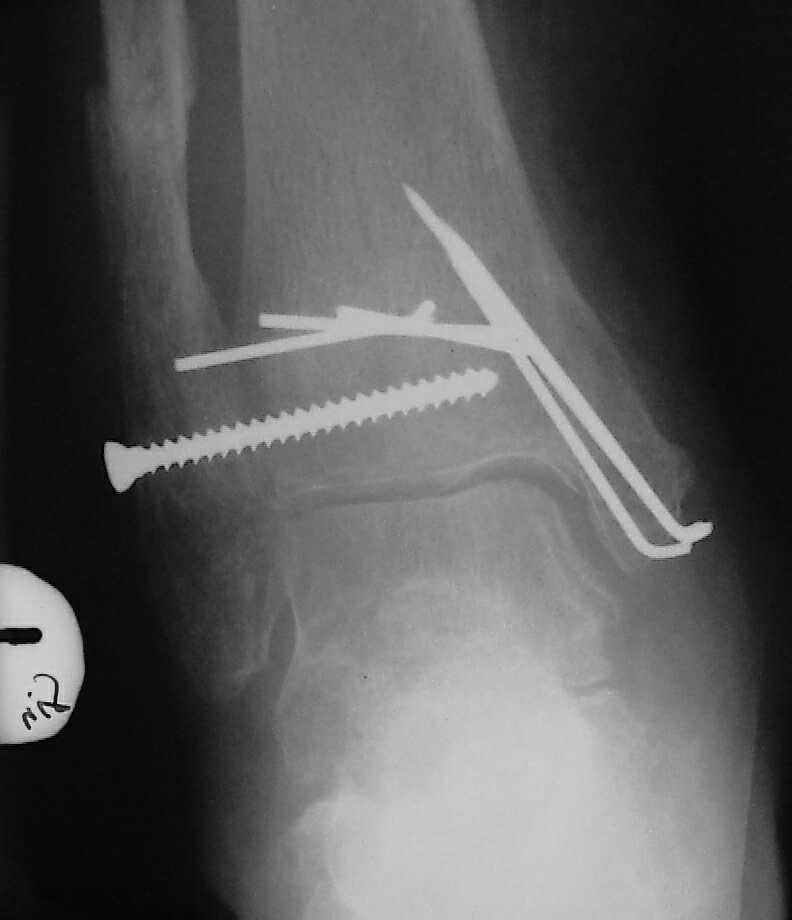

Больная 1936 г.,травма 15 ноября 2003,закрытый трехлодыжечный перелом г/стопного сустава, сахарный диабет.

При поступлении - закрытая репозиция, повторная в связи с большим отеком через неделю, подготовлена к остеосинтезу в первых числах декабря. Заживление без осложнений. Циркулярный гипс - 7 недель, снят,часть спиц удалено 20 февраля т.к.пальпировались под кожей, постепенная нагрузка, проблем нет до середины апреля когда появильсь боли с мед. стороны сустава и локалная гиперемия ( трактовалась как флеботромбоз). Повторное поступление 15 апреля - усиление болей,пов. температура, локально выраженная гиперемия.Локально выделений нет. На RTG - деструкция в области мед лодыжки и заднего края. Сахар крови умеренно повышен. Как трактовать проблему, какой диагноз и тактика лечения? Заранее спасибо, Владимир.

Я бы проблему трактовал как изначально нестабильный и нефункциональный остеосинтез с длительной иммобилизацией у больной с сахарным диабетом, ангиопатией и остеопорозом.

Диагноз я бы поставил: неправильно срастающийся перелом обеих лодыжек и заднего края ББК. Ложный сустав мед. лодыжки? Хронический вялотекущий остеоимиелит голеностопа. Сопутствующий - СД, диабетическая ангиопатия 2.

А почему изначально не сделали хоть по Веберу? В чём смысл 6-ти скусанных спиц? И для чего ввинтили несоответствующий методике шуруп в нижнюю треть остеопорозной, практически отсутствующей лодыжки?

Ретроспективно, на Ваш взгляд, что изменилось бы при остеосинтезе более массивными имплантами?(выбор в пользу спиц как раз и был из-за минимального объема оставляемых имплантов) Иммобилизация 7 недель это очень длительно? Результат на 4 RTG - в чем нефункциональность? - согласен, что репозиция заднего края не была достигнута. Какие признаки ложного сустава мед. лодыжки ?